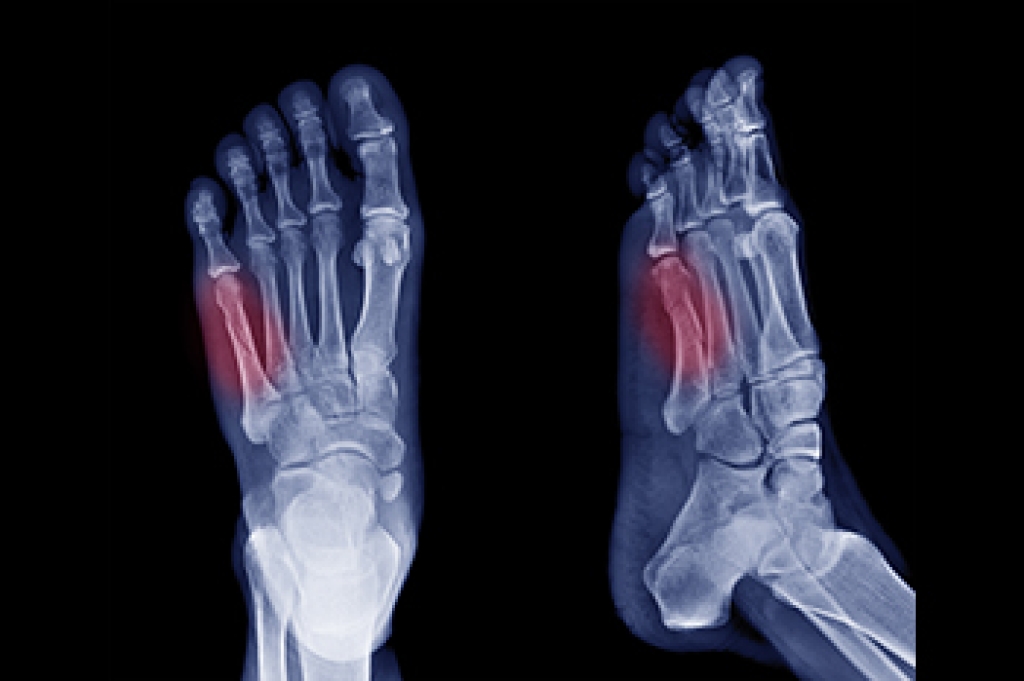

Jones Fracture Symptoms

A Jones fracture refers to a break or crack in the fifth metatarsal bone, located on the outer side of the foot near the ankle. Symptoms typically include pain, swelling, bruising, tenderness on the outer part of the foot, and difficulty walking. Diagnosis usually involves a visit to a podiatrist, who will perform a physical examination, review the symptoms, and take a detailed medical history. To confirm the fracture, imaging tests like X-rays are commonly used. Treatment options depend on the severity of the fracture. For minor cases, rest, mild pain relievers, and possibly a cast or splint may be recommended. Crutches could also be necessary to help avoid putting weight on the affected foot. In more severe cases, surgery may be required to properly heal the bone. Full recovery can take several months, so it is important to allow enough time for the bone to heal completely to prevent further injury. If you suspect you have a Jones fracture, it is suggested that you consult a podiatrist for an accurate diagnosis and personalized treatment plan.

A broken foot is caused by one of the bones in the foot typically breaking when bended, crushed, or stretched beyond its natural capabilities. Usually the location of the fracture indicates how the break occurred, whether it was through an object, fall, or any other type of injury.